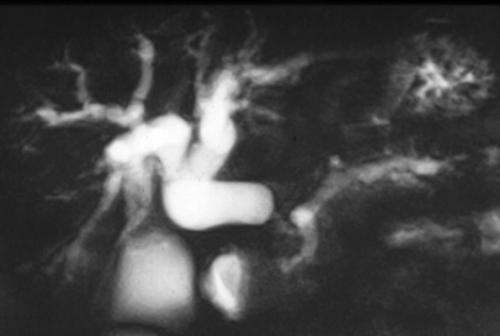

In symptomatic patients or when neoplasms are located within the pancreatic head, bilio-pancreatic duct abnormalities are frequently found. Bilio-pancreatic duct impairment is best depicted by MRCP. This technique does not require intravenous contrast agent administration and provides information similar to endoscopic retrograde cholangiopancreatography (ERCP) including stenosis, occlusion, and duct dilatation, with a high accuracy reported [6]. MRCP clearly identifies the site, extent and degree of the stenosis, and depicts segmental and/or diffuse bilio-pancreatic tree abnormalities related to the size and location of pancreatic neoplasms (Figure 3). Typical ductal changes secondary to pancreatic head neoplasms include: the double duct sign and the mouse tail sign. The former refers to dilatation of both the biliary and pancreatic ducts, the latter is due to the reduction of the bile duct caliber as a result of sudden obstruction at pancreatic head. Moreover, subtle ductal changes provided by MRCP often suggest the diagnosis of small, not well depicted pancreatic tumors and prove to be helpful in the differential diagnosis of chronic pancreatitis in which dilated side branches are seen within, rather than adjacent to, an inflammatory mass [7, 8]. Finally, MRCP, by demonstrating the level of biliary tract obstruction, provides an optimal biliary map useful for appropriate drainage approach (percutaneous cholangiography or ERCP).

Figure 3. a) MRCP shows distal obstruction of the common bile duct and pancreatic duct with upstream dilatation due to head pancreatic neoplasm. b) MRCP shows stenosis of the common bile duct with upstream dilatation due to an infiltrating pancreatic head neoplasm. The main pancreatic duct is slightly dilatated.